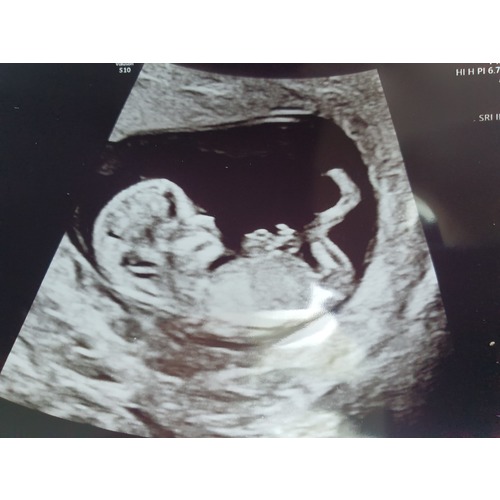

Wat een onwijs duidelijke echo zeg!

Ja eh, ik verschoot er zelf ook van 馃檴

Wauw wat een duidelijke echo! Valt er met 25 weken nog iets van te zeggen? Wij willen het niet weten maar ik ben wel ontzettend benieuwd. 馃槀

Kan iemand bij onze baby een gokje doen? Dit was 24+5. We willen het niet weten officieel maar gokjes vind ik leuk! 馃檲